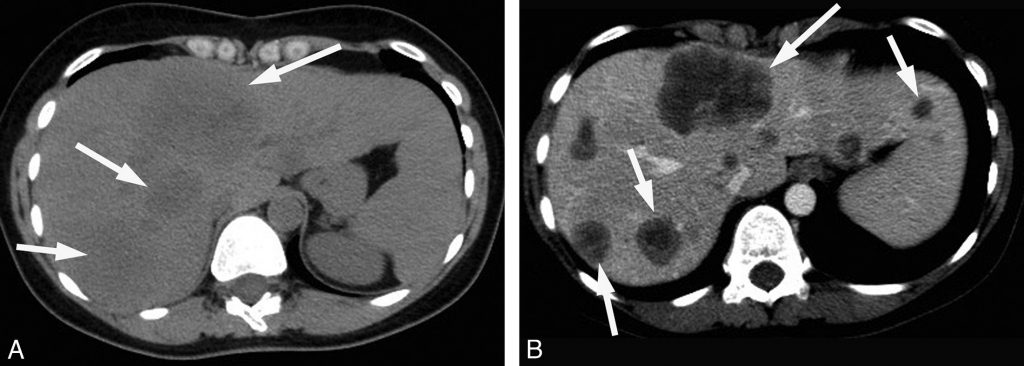

Au scanner, elle est spontanément légèrement hypodense par rapport au foie avec parfois des remaniements hémorragiques (hyper- ou isodenses par rapport au foie) (figure 16.2).

Fig. 16.2. Exemple d’examen scanner d’un CHC typique chez un patient atteint de cirrhose virale C.

(A) Coupe sans injection : tumeur (têtes de flèches) du foie droit avec aspect hétérogène, discrètement hypodense par rapport au foie adjacent. (B) Temps artériel : prise de contraste hétérogène de la lésion alors que le parenchyme hépatique ne se rehausse quasi pas. (C) Temps portal : rehaussement du foie par le flux porte (flèche). Le CHC est isodense au foie avec un rehaussement périphérique (capsule). (D) Temps tardif : rehaussement diffus du parenchyme hépatique et lavage de la lésion.

Source : CERF, CNEBMN, 2022.

Après injection de produit de contraste au scanner ou en IRM, le CHC est caractérisé par un rehaussement important au temps artériel suivi d’un lavage au temps veineux portal ou tardif (figures 16.2 et 16.3), c’est-à-dire que la lésion devient plus hypodense ou hypo-intense que le foie adjacent.